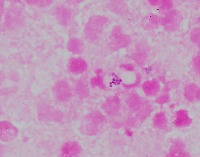

Medical Research: This model can be utilized in the field of medical microbiology and research to classify bacterial strains based on their visual characteristics in lab experiments and for the study of bacterial growth processes.

Healthcare Diagnostics: In healthcare, the "assembly" model could be used to assist in bacterial diagnosis in clinical lab settings, identifying the presence of specific forms of bacteria like Staphylococcus, Streptococcus, B-catarrhalis, Str_pne, and Enterococcus in samples.